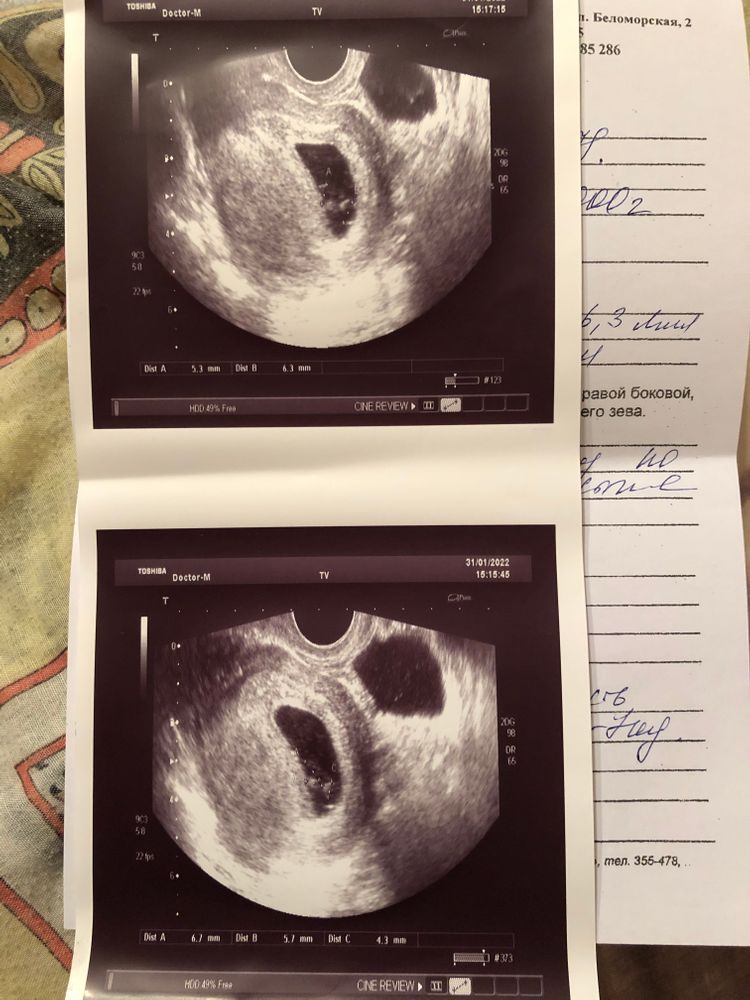

Последние месячные были 1.12, срок должен был быть 8 недель 6дн. На 7-й недели сильно болел живот, обратилась к дежурному геникологу в жк, т.к на учёт у нас ставят только с 8-у недели. Меня осмотрели, сказали все в порядке, назначали через неделю узи. Поставили на учёт, через пару дней пошла на узи, где мне говорят что не слышно сердцебиения. Спрашивают про симптомы тошнит, не тошнит и т.д, нет ли выделений(выделений нет, тошнить продолжает, сплю постоянно, живот не тянет, температуры нет, да и в целом ни единого признака замершей нету). Меня начали успокаивать и отправили к доктору, сказали есть вероятность что срок маленький, и ставят мне срок 5 недель 6 дней. Пошла к доктору, доктор сказала делать ХГЧ в динамике, и через неделю на повторное узи. Сделала на след день ХГЧ, не выдержала и через три дня(сегодня) я пошла на узи в другую клинику. Там мне сразу же сказали, что плод не развивается, и ставят срок 6-7 недель, так же размер эмбриона(ктр) при этом 3,9, а три дня назад был 3,22. Получается по размеру это и есть 6-7 недель, но плод увеличился же ведь… Меня и слушать сегодня не хотели, повели сразу к доктору, тот говорит надо делать срочно медикаментозный аборт. Я говорила про то, что второе ХГЧ ещё не делала, на это мне говорят, что уже бессмысленно его ждать все понятно, на данном сроке сердцебиение должно быть ясным. Записали на завтра на аборт. Я вся как в тумане, решила поехать и сделать ещё одно узи в другой клинике. Прихожу, начинаю объяснять, мол почему ставят разные сроки и размеры, спрашивать почему симптомы беременной у меня не пропали, а симптом замершей нет никаких. Говорят на это, что это аргумент. Пошли на само узи, тут же мне показывают что у меня два пя, и что у меня однозначно неразвитая беременность, ставят диагноз что у меня двойня и замершая. Я снова, как в тумане потерялась, забыла про все вопросы, в расстройстве, ушла. И только потом до меня дошло, что вероятно с меня хотели содрать деньги(за аборт и восстановление). Завтра на аборт не пойду, сделаю второе ХГЧ, и после на ещё одно узи. Надеюсь на чудо.

Прикреплю фото всех узи. И да, ХГЧ первое пришло там результат на 76037, результат в пределах нормы 7-9 недели.